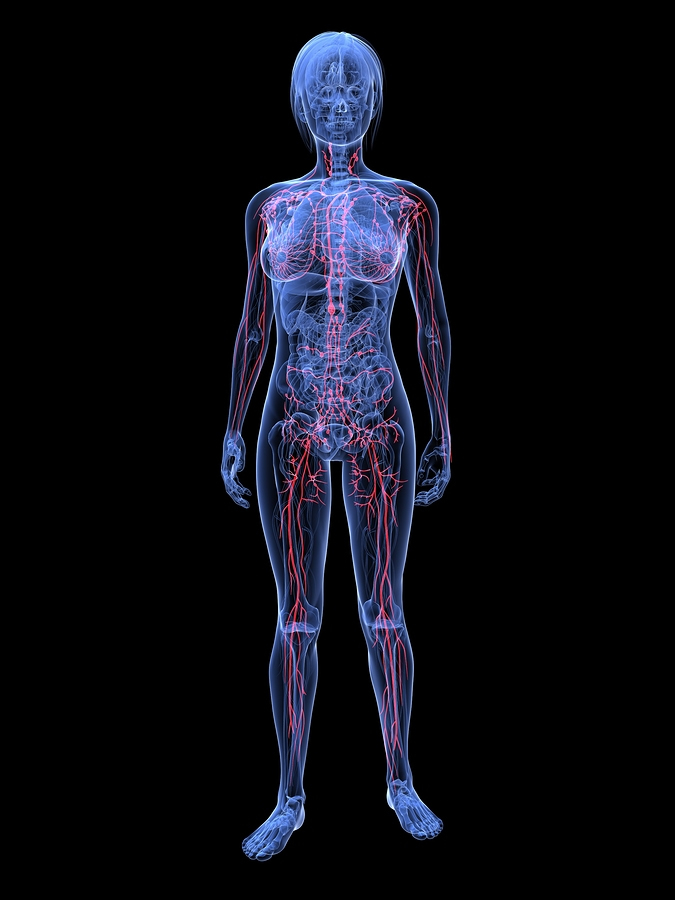

BodyTalk for Lymphatic Drainage

BodyTalk has its own unique process to help stimulate sluggish lymphatic movement in the body and drain tissues of excess fluid. It is called the VELTHEIM METHOD OF LYMPHATIC DRAINAGE, named after John Veltheim, the founder of BodyTalk.

Like standard Manual Lymphatic Drainage methods, this technique has been used to decrease swelling in tissues, improve mobility, enhance immune functioning, and draw toxins from the body. It can be helpful in addressing a range of health conditions including arthritis, fibromyalgia and chronic fatigue syndrome. As there is a theory that poor circulation of fluids and lymph underlies a host of conditions from cellulite to cancer, lymphatic drainage could support a number of other health issues as well.